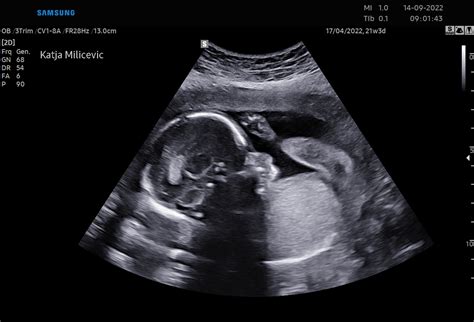

Pomembna novost v tem tednu je nadaljnji razvoj senzoričnih sposobnosti. Otrokov obraz je skoraj v celoti oblikovan, kar mu omogoča, da že kaže obrazne mimike. Razvijajo se čutila, zaradi česar postaja otrok občutljiv na okolico. Lahko zazna zvoke, vključno s srčnim utripom mamice in zvoki iz zunanjega sveta. Glasni zvoki ga lahko prestrašijo, kar se lahko kaže kot trzljaj telesa, kar je mogoče opaziti na ultrazvočnem pregledu. Poleg tega otrok že zaznava svetlobo in temo; če sonce sije na vaš trebuh, lahko plod reagira na to spremembo.

Čeprav se nosečnost šteje od zadnje menstruacije, za medicinske namene in spremljanje razvoja ploda stroka uporablja tedne. V drugem trimesečju, kamor sodi 17. teden, se običajno opravi ultrazvočni pregled morfologije ploda okoli 20. tedna. Ta pregled omogoča natančno oceno razvoja vseh organov in telesnih struktur.